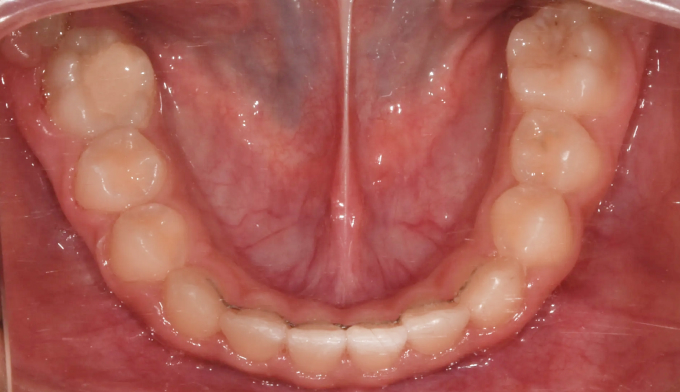

초등학교 4학년 남학생이 이가 고르지 못하고 송곳니가 나지 않는다고 합니다.

엑스레이를 찍어보니 치아가 나올 공간이 많이 부족하여 이가 고르지 못하고 송곳니가 나올 공간도 부족해 보였습니다. 정상적인 맹출 순서가 어긋나다보니 치열의 비대칭도 관찰됩니다.

약 8개월간의 공간확장치료를 통하여 이가 배열되고 송곳니가 나올 공간을 만들어주었습니다.

공간 확보 후 치아를 배열하여 교정 마무리 하였습니다.